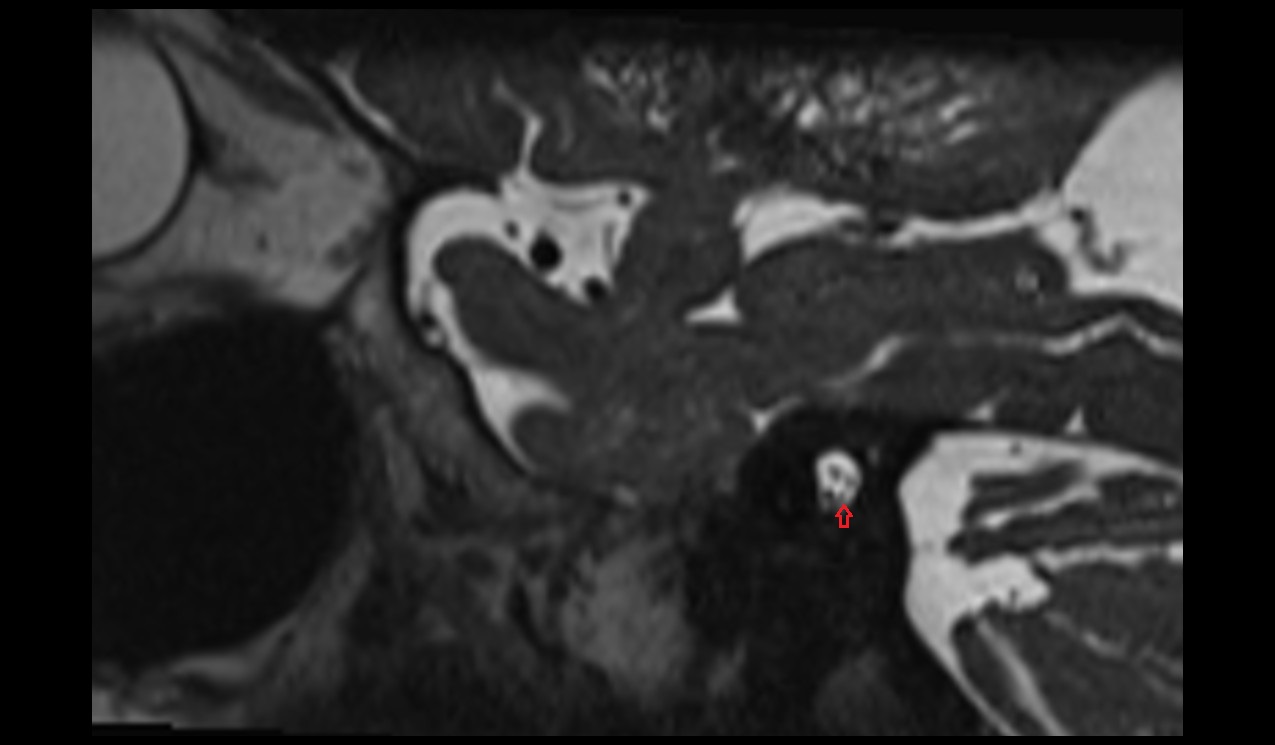

- Jugular foramen

- jugular foramen pars nervosa

- Jugular foramen pars vascularis

- Abducens nerve (Cranial nerve VI)

- Glossopharyngeal nerve (Cranial nerve IX)

- Vagus nerve (Cranial nerve X)